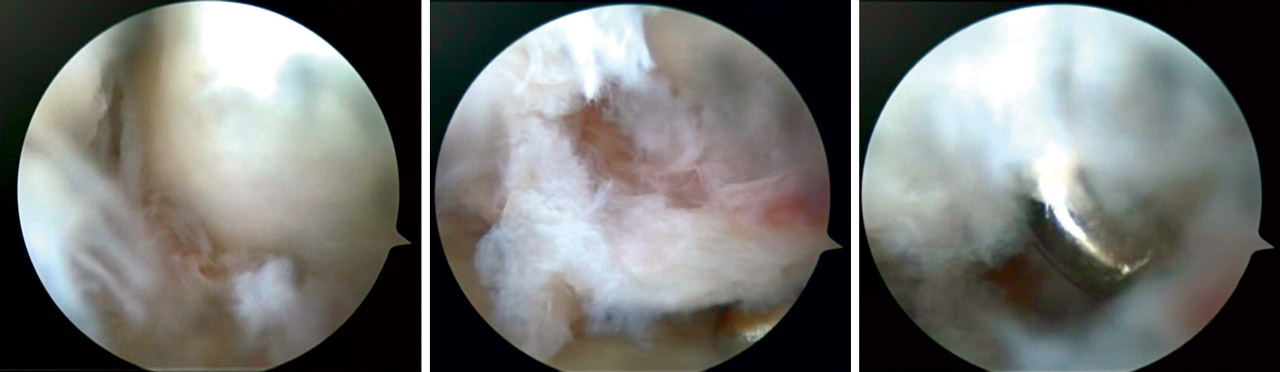

Lesiones del complejo fibrocartílago triangular

En roturas periféricas se realizaron suturas directas anclando el fibrocartílago a la cápsula articular. En las roturas foveales se procedió a la reinserción foveal con anclaje óseo mediante dispositivo PushLock® (Arthrex) (Figura 8). Ambas técnicas se realizaron de forma artroscópica.

Lesiones del ligamento lunopiramidal

En casos de lesión completa de grado III y IV realizamos desbridamiento artroscópico y fijación interna mediante tornillo percutáneo semilunopiramidal (Figura 9).

La extracción del tornillo semilunopiramidal se realizó a los 4 meses de la cirugía.